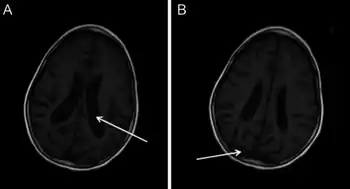

- MRI